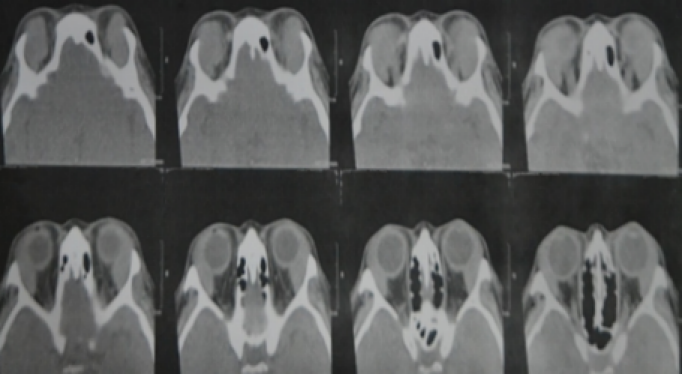

Our assessment at this point was an orbital lymphoproliferative disorder, bilateral; probably lymphoma with mechanical ptosis with good levator function, right upper eyelid; and suspicion of glaucoma in both eyes. To support our assessment, we needed imaging studies, which had fortunately already been ordered previously by the glaucoma specialist. On plain CT scan, we noted a homogenous mass with molding or contouring around the orbital structures.

On coronal view, we noted homogenous masses that mold around the globe and recti, and this also confirmed on axial cuts. This not only supported our assessment, it also effectively ruled out the other 3 differential diagnoses we had earlier (Figure 2 [Fig. 2], Figure 3 [Fig. 3]).

Figure 2: A coronal view of a plain orbital CT scan of the patient showing a homogenous mass molding around the globe and recti bilaterally

Figure 3: An axial view of a plain orbital CT scan of the patient showing a homogenous mass molding around the globe and recti bilaterally

Molding around orbital structures is the radiologic hallmark of orbital lymphoproliferative disorders, but it will not differentiate between benign and malignant disease. Consequently, our assessment was maintained.